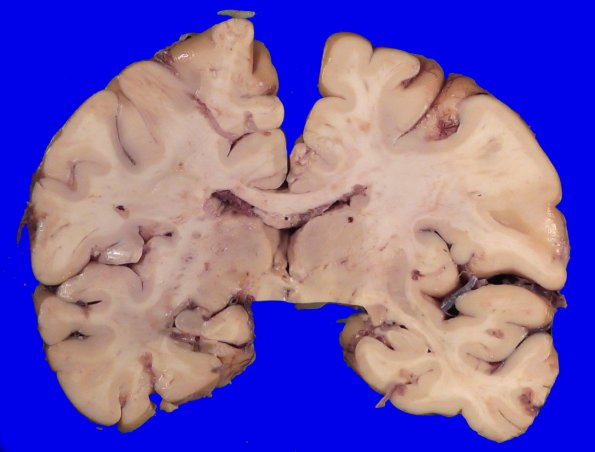

Case 16 History ---- The patient was a 45-year-old woman with retinal vasculopathy with cerebral leukodystrophy (RVCL) complicated by bilateral ocular hypertension, vascular dementia and ischemic colitis. Additionally, she had previously been diagnosed with nodular regenerative hyperplasia of her liver with portal fibrosis. She was symptomatic for many years, with progressively worsening generalized weakness, abdominal pain, severely decreased oral intake, nausea, and weight loss. She also experienced double-vision, severe headaches, and vertigo. After several interventions were attempted to address her malnutrition and intractable nausea, she elected to forgo further intervention and enter hospice care in October 2021. She experienced continued progression of her headaches, abdominal pain, and weight loss related to her condition. She passed away in June 2023. ---- At autopsy the unfixed brain weighed 1040g. Although the patient had considerable pathophysiology, the external cortex, brainstem, cerebellum and spinal cord were only remarkable for mild gyral atrophy.. ---- 16A1 Coronal sections were largely devoid of grossly visible while matter lesions.